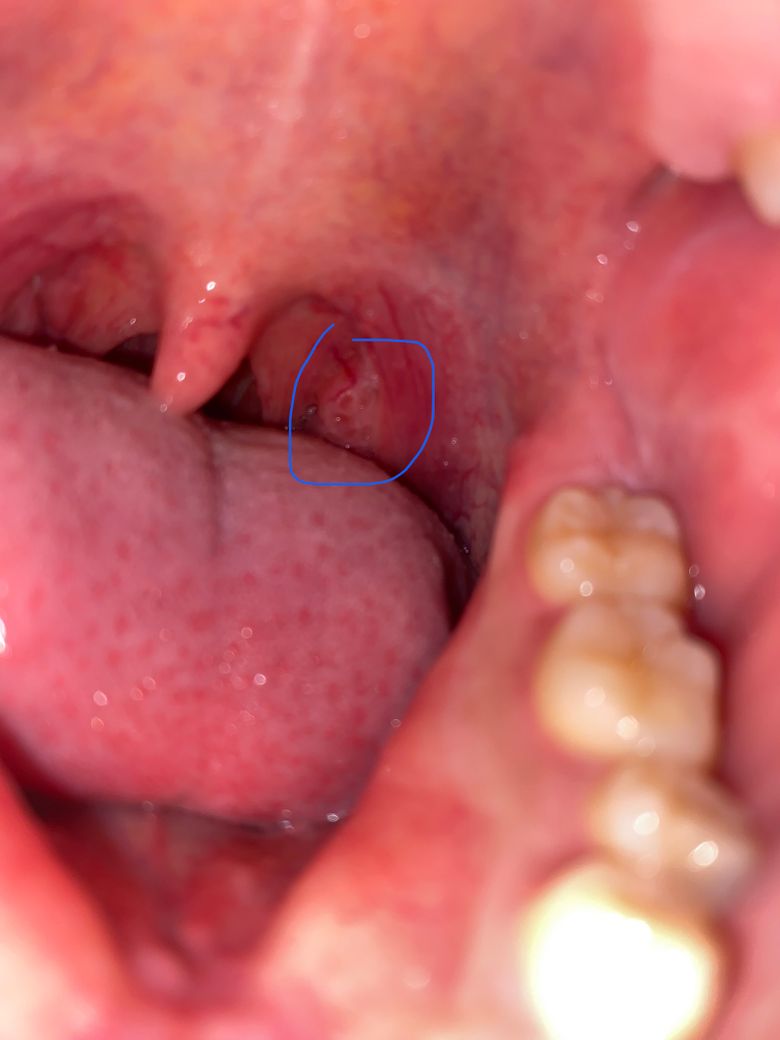

여기부분 반대쪽이랑 다른데 뭔가요? 심각한거면 병원에가야하나요

뭔지 모르겠습니다 요즘 사랑니 밑에에 뭐도 났는데 3주가 지나도 안사라집니다

연조직에 손상이 있어보이기는 합니다. 정확한 것은 구강내과나 이비인후과 가보시는 게 좋습니다.

심각한 상태는 아니고 뜨거운음식에 저부위가 화상을 입은거 같으니 당분간은 자극적인 음식은 피해주시는게 좋을것같습니다.

구강 내 연조직 질환일 가능성이 있어 보입니다. 해당 부위가 2주 이상 지속되고 불편감이 지속적으로 나타난다면 가까운 치과 방문 후 검사를 해보는 것이 필요합니다. 따라서 지금 상태라면 치과 방문 후 검사를 한 번 받아보는 것이 좋습니다.

해당 부위 표면의 상피 염증이 아닐까 싶습니다만 정확한 검사를 위해서는 치과보다는 이비인후과 내원을 권유드립니다.